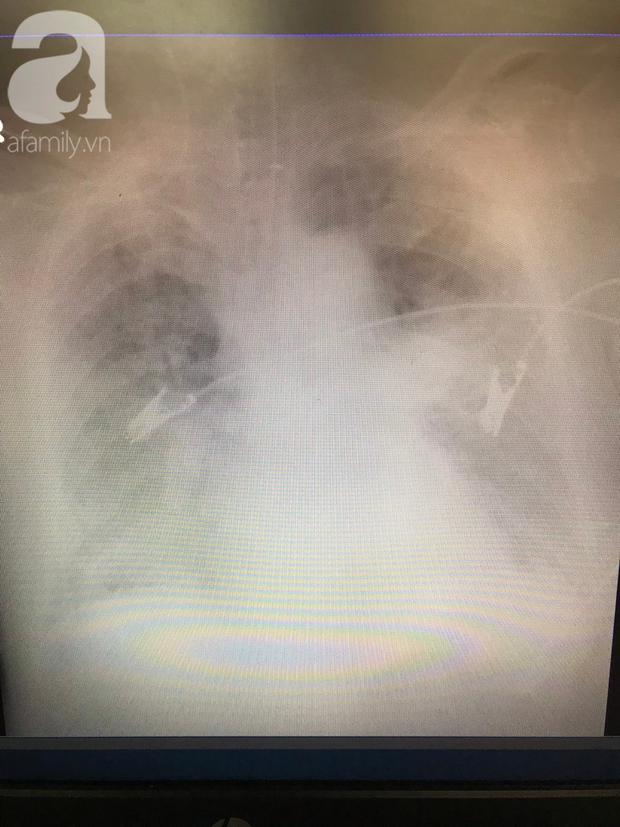

06/05/2020 00:28TP.HCM: Hàng loạt bệnh nhân hít sặc khi ăn uống, 3 người nguy kịch

Bác sĩ Hoàng Ngọc Ánh, Phó Trưởng khoa ICU, Bệnh viện (BV) Thống nhất (TP.HCM) cho biết trong thời gian qua, đơn vị đã tiếp nhận nhiều trường hợp bệnh nhân bị hít sặc rất nặng, thậm chí dẫn đến tử vong.

Đơn cử trong tháng gần đây có 4 trường hợp gồm 3 nam, 1 nữ, tuổi từ 82-88. Trong đó có 3 ca di chứng tai biến mạch máu não .

Các bệnh nhân đến khoa trong tình trạng suy hô hấp, phải hỗ trợ thở máy. Tiến hành nội soi súc rửa, bác sĩ thấy có dịch dạ dày lợn cợn, sữa, thậm chí có cả chả và trứng bên trong... Vì tình trạng đa số đều nặng nên sau một thời gian cố gắng điều trị, chỉ một trường hợp may mắn sống sót, còn 3 trường hợp người nhà xin về.

Từ những sự việc đau lòng trên, bác sĩ Hoàng Ngọc Ánh cho biết hít sặc là 1 tình huống khẩn cấp có thể đe dọa tính mạng, khi dị vật rơi vào đường hô hấp gây tắc nghẽn. Đây là 1 sự cố hay biến cố có thể xảy ra ở mọi lứa tuổi, đặc biệt nguy hiểm hơn đối với người cao tuổi.

Theo thống kê, ước tính khoảng 10-15% viêm phổi cộng đồng là do hít sặc.

Hít sặc gây viêm phổi là nguyên nhân tử vong chủ yếu ở những bệnh nhân khó nuốt. Viêm phổi do hít sặc chiếm khoảng 18% ở những bệnh nhân được chăm sóc tại nhà.

Triệu chứng của hít sặc là ho, khò khè, khó thở, tím tái đối với những trường hợp nặng. Tuy nhiên các triệu chứng do hít phải thường bị bỏ qua và điều trị sơ sài vì ít nghĩ tới.